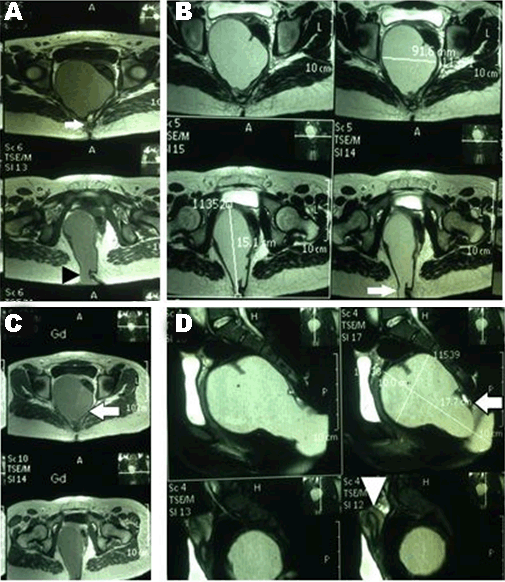

Case 1 History and Examination The patient had a history of a small bulge in the perineum on the right side and a small sinus just below her coccyx during her lifetime. She had no leg pain or paresthesias, no difficulties in urination or defecation, no weight loss, and was able to walk with no difficulties. The patient had an uneventful medical and surgical history with a negative parental consanguinity and a negative family history for same. No irregularities were marked in the menstrual cycle since her menarche at 12 years. In the last two years, she had a decrease in the duration of bleeding (from seven to three days) but with a normal amount of flow. On physical examination, lower limbs revealed normal muscle tone and power, intact sensation, normal reflexes and intact sphincters and rectal mucosa, which was further confirmed by digital rectal examination. A large cystic mass was observed pushing the rectum posteriorly with the mucous membrane moving over it. Diagnostic evaluation Surgery The wound was packed with gauze flavored with iodine and left for secondary healing to take place with regular dressing till 21 days. Histopathological examination Microscopically, the sections showed mature respiratory mucosa, squamous epithelium, mucinous gland and glial elements associated with fibrofatty tissue, bundles of nerve fibers and smooth muscle. It also contained coccygeal bone. The diagnosis was mature cystic teratoma. Outcome Magnetic resonance imaging of pelvis and lumbosacral region revealed it to be free of mass with the restoration of the position of the rectum, bladder and the site of coccygectomy (Figure 4). Case 2 History and Examination The patient had a history of small sinus without discharge below the coccyx. She had no leg pain or paresthesias, no difficulties in urination or defecation, no weight loss and no walking difficulties. The patient had uneventful medical and surgical history with a negative parental consanguinity and a negative family history for same. Her menstrual cycle was regular, with no change in the amount or duration. Her menarche started at 15 years. Physical examination of lower limbs revealed normal muscle tone and power, intact sensation, normal reflexes, intact anal sphincter and normal rectal mucosa, which was further confirmed by digital rectal examination. A cystic mass was found to be pushing on the rectum posteriorly; the mucous membrane was found moving over it. Diagnostic evaluation Magnetic resonance imaging of pelvis and lumbosacral region revealed a large (17×15×10 cm) lobulated outline, hyperintense signal on T1- and T2- with a small (2×10 mm) fatty component near the coccyx, arising from the anterior of lower sacrum and extending posteriorly to the gluteal region more on the right side below the coccyx to the pelvis. It caused displacement of the rectum posterolaterally and uterus and urinary bladder anteriorly. No enhancement was seen after gadolinium contrast (Figure 5). Surgery Histopathological examination A small cyst lined by ciliated epithelial cells was found on one side and squamous epithelial cells on the other, with enteric glandular component seen in the wall of the main cyst. A piece of the bone was present. The diagnosis was chronically inflamed pilonidal sinus with mature cystic teratoma. Outcome | ||||||